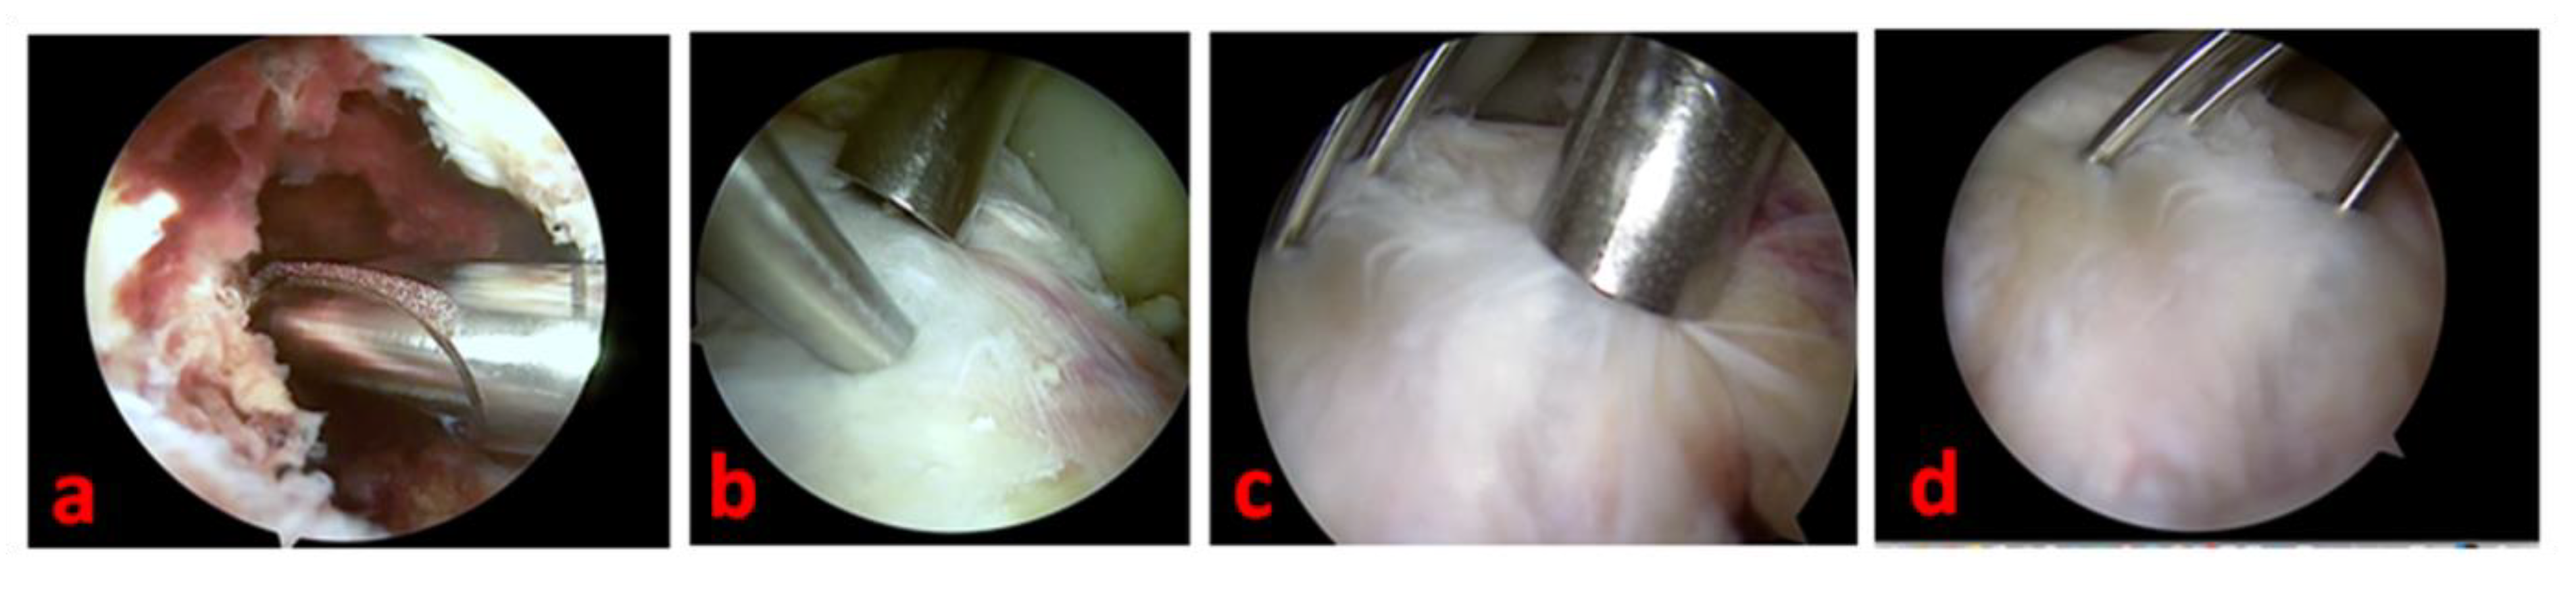

Standard anteromedial, anterolateral, and superolateral arthroscopic portals allow for full access to knee visualization, favoring a complete and direct visualization of the tibial eminence avulsion. We prefer to avoid the trans-tendinous Gillquist central portal [34], but we systematically use a modified Patel’s medial mid-patellar (superomedial) portal [35] or more patient-specific accessory ones if necessary to address associated intraarticular lesions. A thorough hematoma and blood clot washing and a selective Hoffa’s pat debridement are performed to achieve clear visualization of the joint. Care should be taken to avoid the complete removal of Hoffa’s pad to limit the post-operative knee stiffness. The eventual interposition of the intermeniscal ligament or the entrapment of the anterior horn of the medial or lateral meniscus in the fracture site can be easily managed by extracting them with an arthroscopic probe or a pick. The concomitant intraarticular lesions are arthroscopically addressed and managed according to the consolidated surgical modalities. We perform the debridement of the inflammatory tissue in the fracture site with a full-radius shaver blade and the reduction in the fracture by using a less-invasive bone impactor. With the knee flexed to 90°, the fracture fragments are then synthesized (under fluoroscopic control) with three thin Kirschner wires (maximum diameter: 2 mm) inserted in a proximal–distal direction in a cross-shaped geometry and guided by 2.4 mm cannulated aimers (Figure 3).

Figure 3.

Arthroscopic view of tibial spine avulsion management of the left knee of a 16-year-old female patient—(a): light fracture site debridement is necessary to grant adequate visualization; (b): the reduction of the fracture is facilitated by using a less-invasive bone impactor; (c): a cannulated aimer is a useful tool to drive the Kirschner wires positioning; (d): the osteosynthesis is performed and completed by positioning three thin Kirschner wires in a cross-shaped geometry.

Cannulated aimers are also useful in performing a moderate compression of the fracture fragments while inserting the Kirschner wires. Two K wires are inserted through the superolateral portal to reduce the tibial intercondylar eminence (and mimic the orientation and the force lines of ACL fibers), and 1 K wire is inserted through the superomedial portal [35]. According to our experience, the Kirschner wires should ideally reach the opposite tibial cortical surface to strengthen the osteosynthesis mechanism. Caution must be taken to prevent iatrogenic damage to the external popliteal sciatic nerve; for this reason, we suggest pre-determining and equalizing the length of the Kirschner wires after the careful positioning of the first one under fluoroscopic control.

Under arthroscopic and fluoroscopic visualization, we completely extend the knee to confirm the effectiveness of reduction and stability. The Kirschner wires are externally cut (by maintaining a 2–3 cm straight external portion—essential for the subsequent removal) and curved (Figure 4).